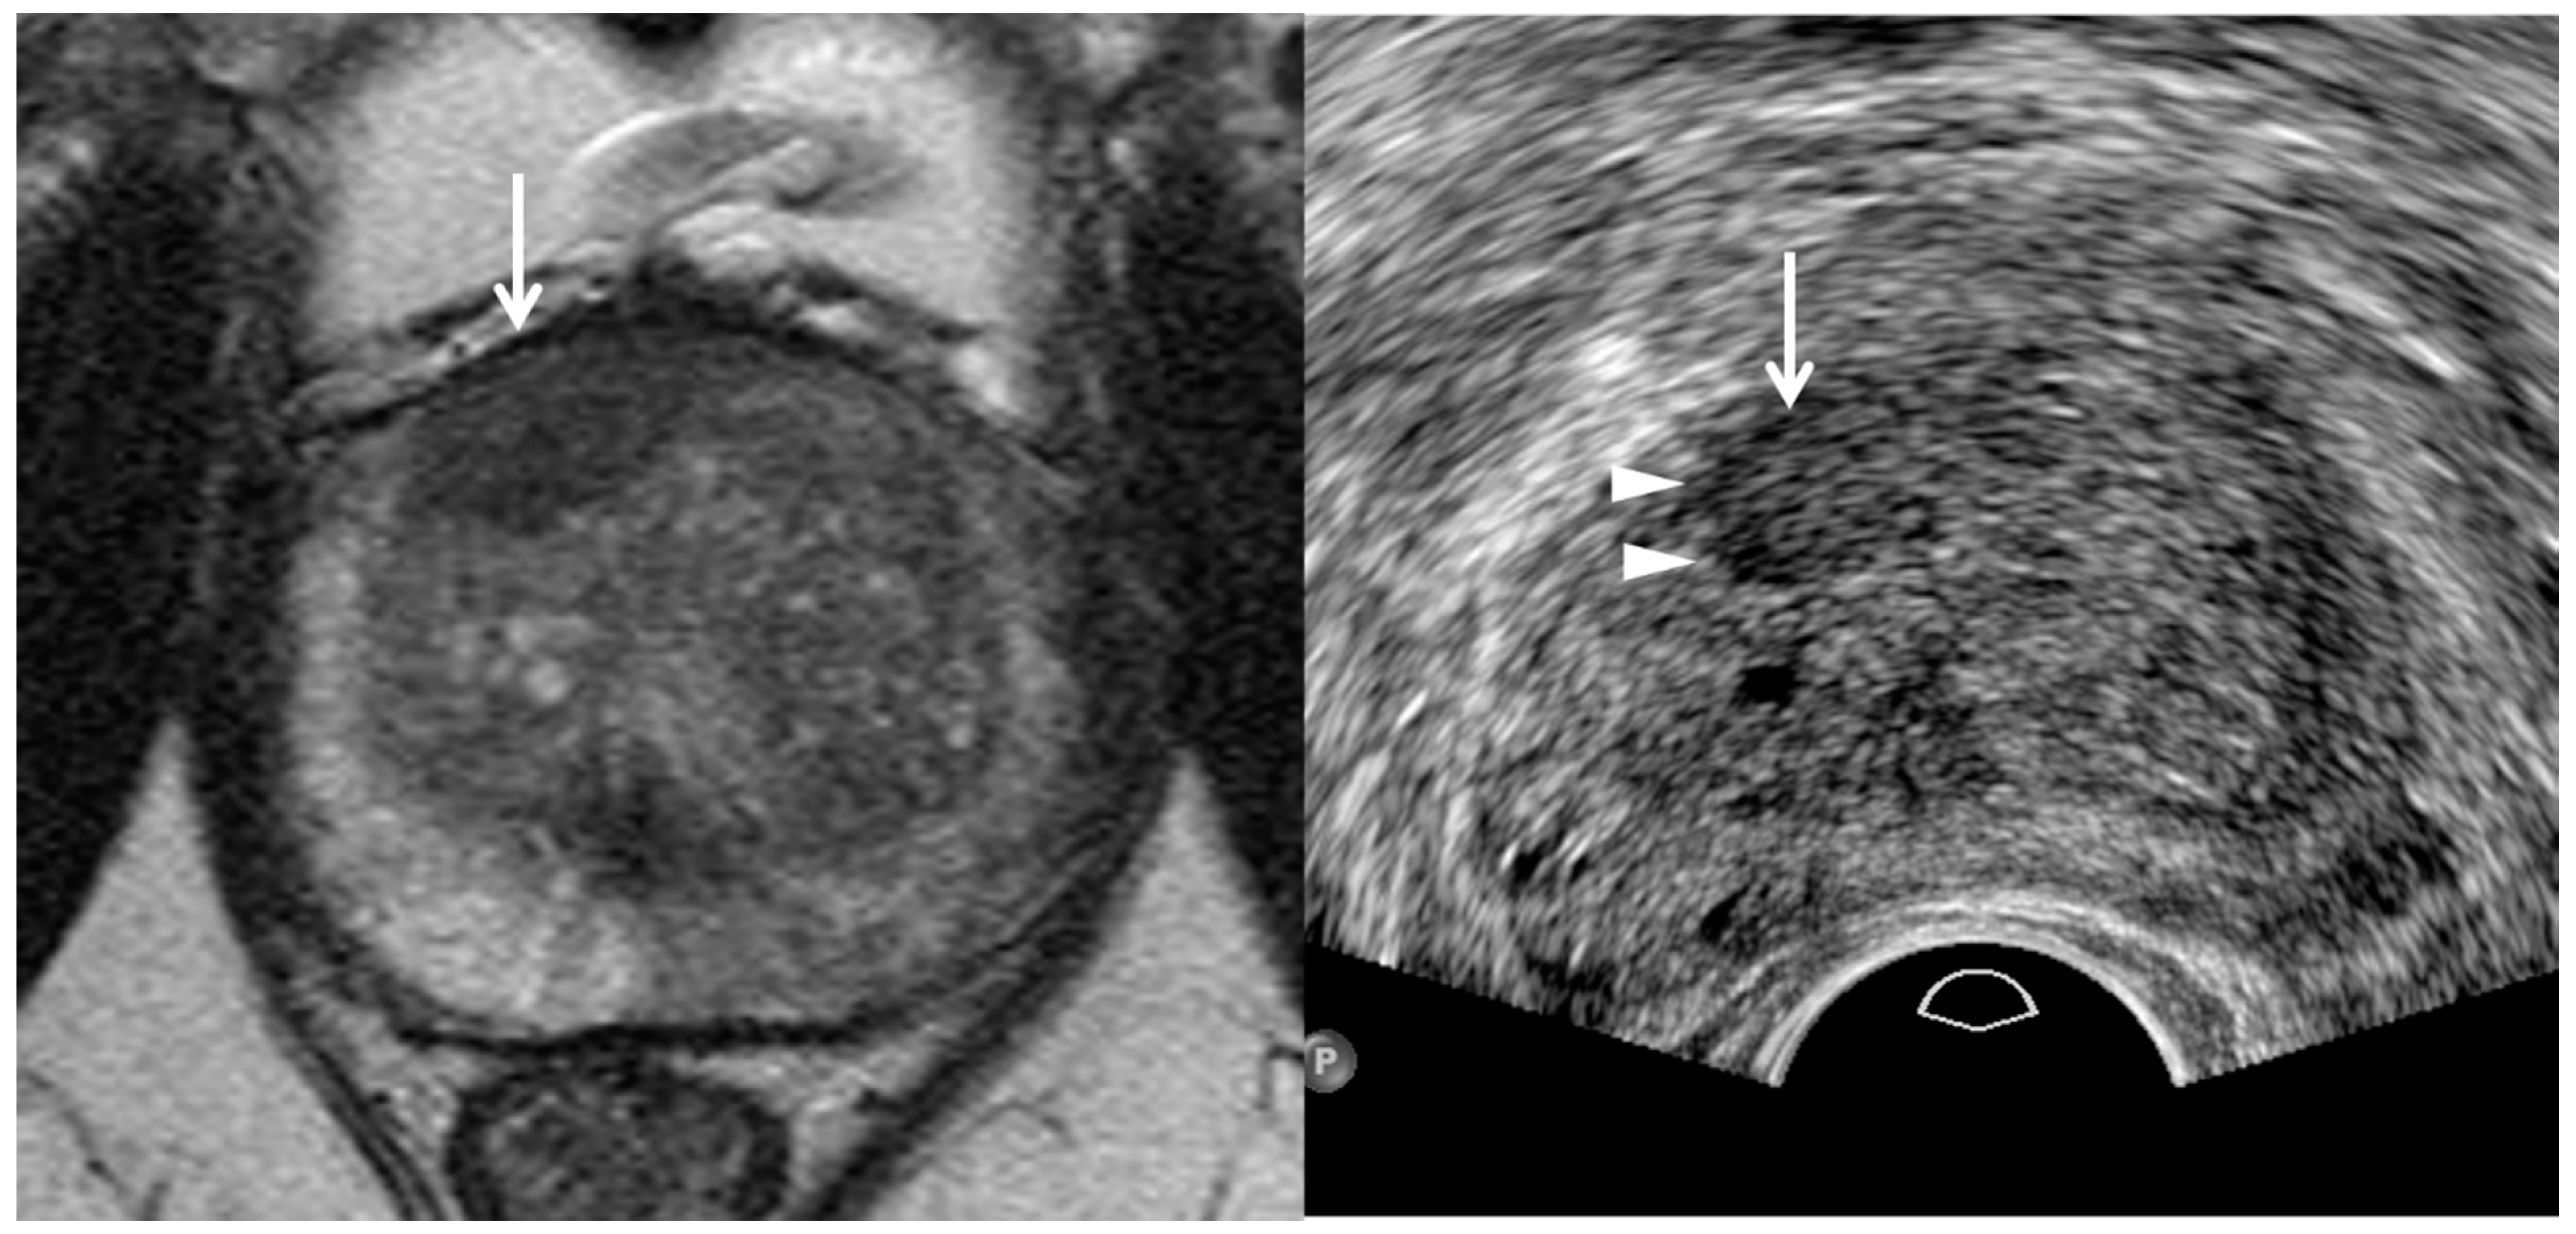

3. TRUS Imaging Features

| Tumor Location/Morphology | MRI | TRUS |

|---|---|---|

| Scan axis to urethra | Perpendicular | Oblique |

| Anterior 1/3 location | Base and mid-gland | Mid-gland and apex |

| Middle 1/3 location | Same location | Same location |

| Posterior 1/3 location | Apex and mid-gland | Mid-gland and base |

| Tumor size | Different size | Different size |

| Tumor shape | Different shape | Different shape |